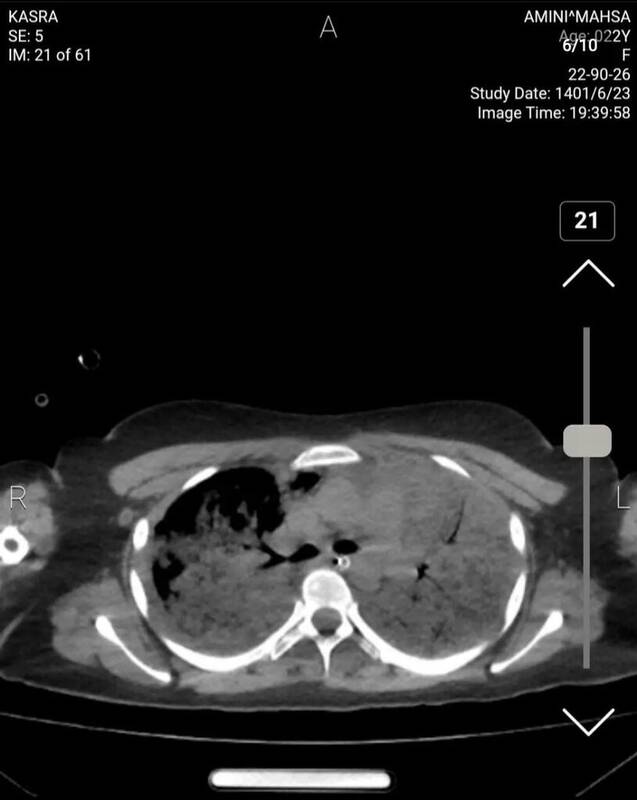

برای بررسی وضعیت ریه بیمار نیز با تخصص رادیولوژی گفتوگو کردیم که وی توضیح میدهد: در سیتیاسکن ریه شواهد کانتیوژن یا له شدگی بافت ریه مشاهده میشود که پس از «سی پی آر» رخ میدهد و ممکن است در هر بیماری رخ دهد و این موضوع غیرطبیعی نیست.